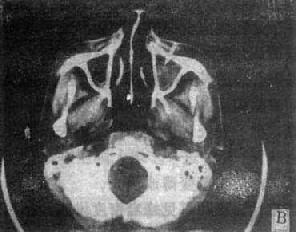

图5-2-5 鼻窦、鼻咽和喉部CT扫描

右上颌窦癌,肿块突入鼻腔和鼻咽部(↓)双上颌窦炎,右侧明显并积液(↑)鼻咽癌,右侧咽壁变直,咽鼓管开口和侧隐窝消失(↑)鼻咽癌,左侧咽壁肿块向咽腔内突起,咽旁间隙侵犯,双上颌窦受累右侧声门癌,右声带增厚并有结节状突起(↑),声门裂变形声门下癌,气管左侧软组织肿块,气道受压变窄

(一)鼻窦肿< 良性病变常见为粘液囊肿和息肉,肿块较小者呈窦腔内密度均匀结节影,边缘光滑锐利,骨壁无破坏;较大者占据整个窦腔,并压迫窦壁使之膨隆扩大,窦壁变薄。一般囊肿的CT值较低。息肉为实性肿块密度较高。恶性肿瘤以鼻窦癌和转移瘤为主。其肿块轮廓多不规则,常伴有窦壁骨质破坏;并伸向鼻咽、鼻腔和眼眶,于该区出现软组织肿块,引起周围脂肪层消失,从而为根治手术或放射野的确定提供可靠的依据(图5-2-5)。

(二)鼻窦炎 急、慢性鼻窦炎均显示窦腔混浊,密度增加,粘膜增厚,窦壁可有骨质侵蚀或硬化。鼻窦炎一般X线检查作出明确诊断者,无需再行CT扫描检查(图5-2-5)。

恶性肿瘤以鼻咽癌为主,偶为肉瘤。CT横断面扫描可见鼻咽侧后壁增厚或有软组织块影突出入鼻咽腔,引起咽腔变窄变形,咽鼓管开口和侧隐窝闭塞(图5-2-5)。咽旁侵犯可见咽旁脂肪间隙消失(图5-2-5)。翼腭窝和颞下窝受累,该区见软组织肿块,可有骨质破坏。肿瘤向颅内蔓延可见颅底骨质破坏,并于海绵窦、鞍旁或眶尖见到强化结节。CT扫描有助于鼻咽癌的诊断和分期、制定治疗计划和观察治疗效果。